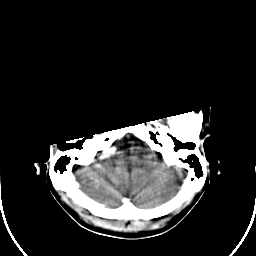

Sarcoma: Roentgen-ray CT -- Slice #4

[Home][Help][Clinical] Slice 4